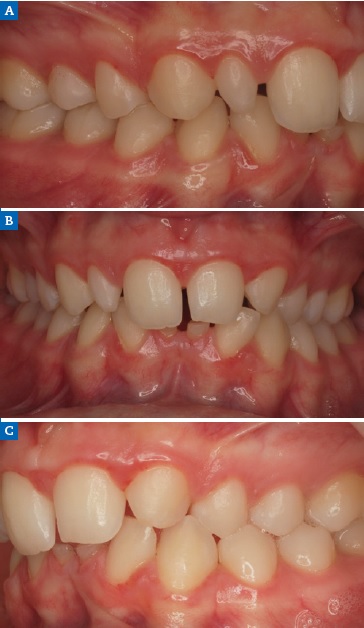

Figure 17 Case 3: Initial intraoral views of the (A) right, (B) frontal, and (C) left aspects before the orthodontic treatment, revealing a Class I right molar, a Class II left molar, and a deep bite.

Figure 18 Case 3: Intraoral views of the (A) right, (B) frontal, and (C) left aspects after the orthodontic treatment.

A 19-year-old female patient presented with primarily esthetic concerns. An intraoral examination revealed a Class I right molar, a Class II left molar, and a deep bite (Figure 17). Orthodontic treatment was performed to obtain bilateral Class I molar and canine relationship and, in turn, improve the overbite and remove the traumatic occlusion responsible for the gingival recession on the left mandibular incisor. Bolton’s anterior analysis confirmed a dental discrepancy in the anterior sector to mandibular excess with a proportion of 83.1% (13, 12, 11, 21, 22, 23 / 43, 42, 41, 31, 32, 33). It was caused by the maxillary dental microdontia and the need to carry out esthetic restorations in the upper arch. A space was created on the distal surface of both microdontic lateral incisors to establish the Bolton’s proportion17 (Figure 18). After orthodontic treatment, shade selection was accomplished using a Vita Shade Guide (Figure 19), and dental bleaching was performed to optimize the harmony of the smile.